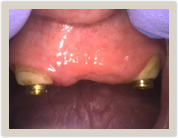

Patient was very unhappy with her broken down teeth, but loves her new smile. The denture is anchored by two of her own teeth with Locator attachments.

Locater Females Locater Males

P3944_ss7473cs_t P3944_ss7473zs_t

Prepped denture Locater males on Females

Dentures are snap in secured with Locater attachments. The female locaters are placed with no need for anesthetic on previously root canaled teeth. The Locater males are snapped onto the Locater females and then the Locater males are incorporated into the prepared denture with denture acrylic to create a snap on secured denture!